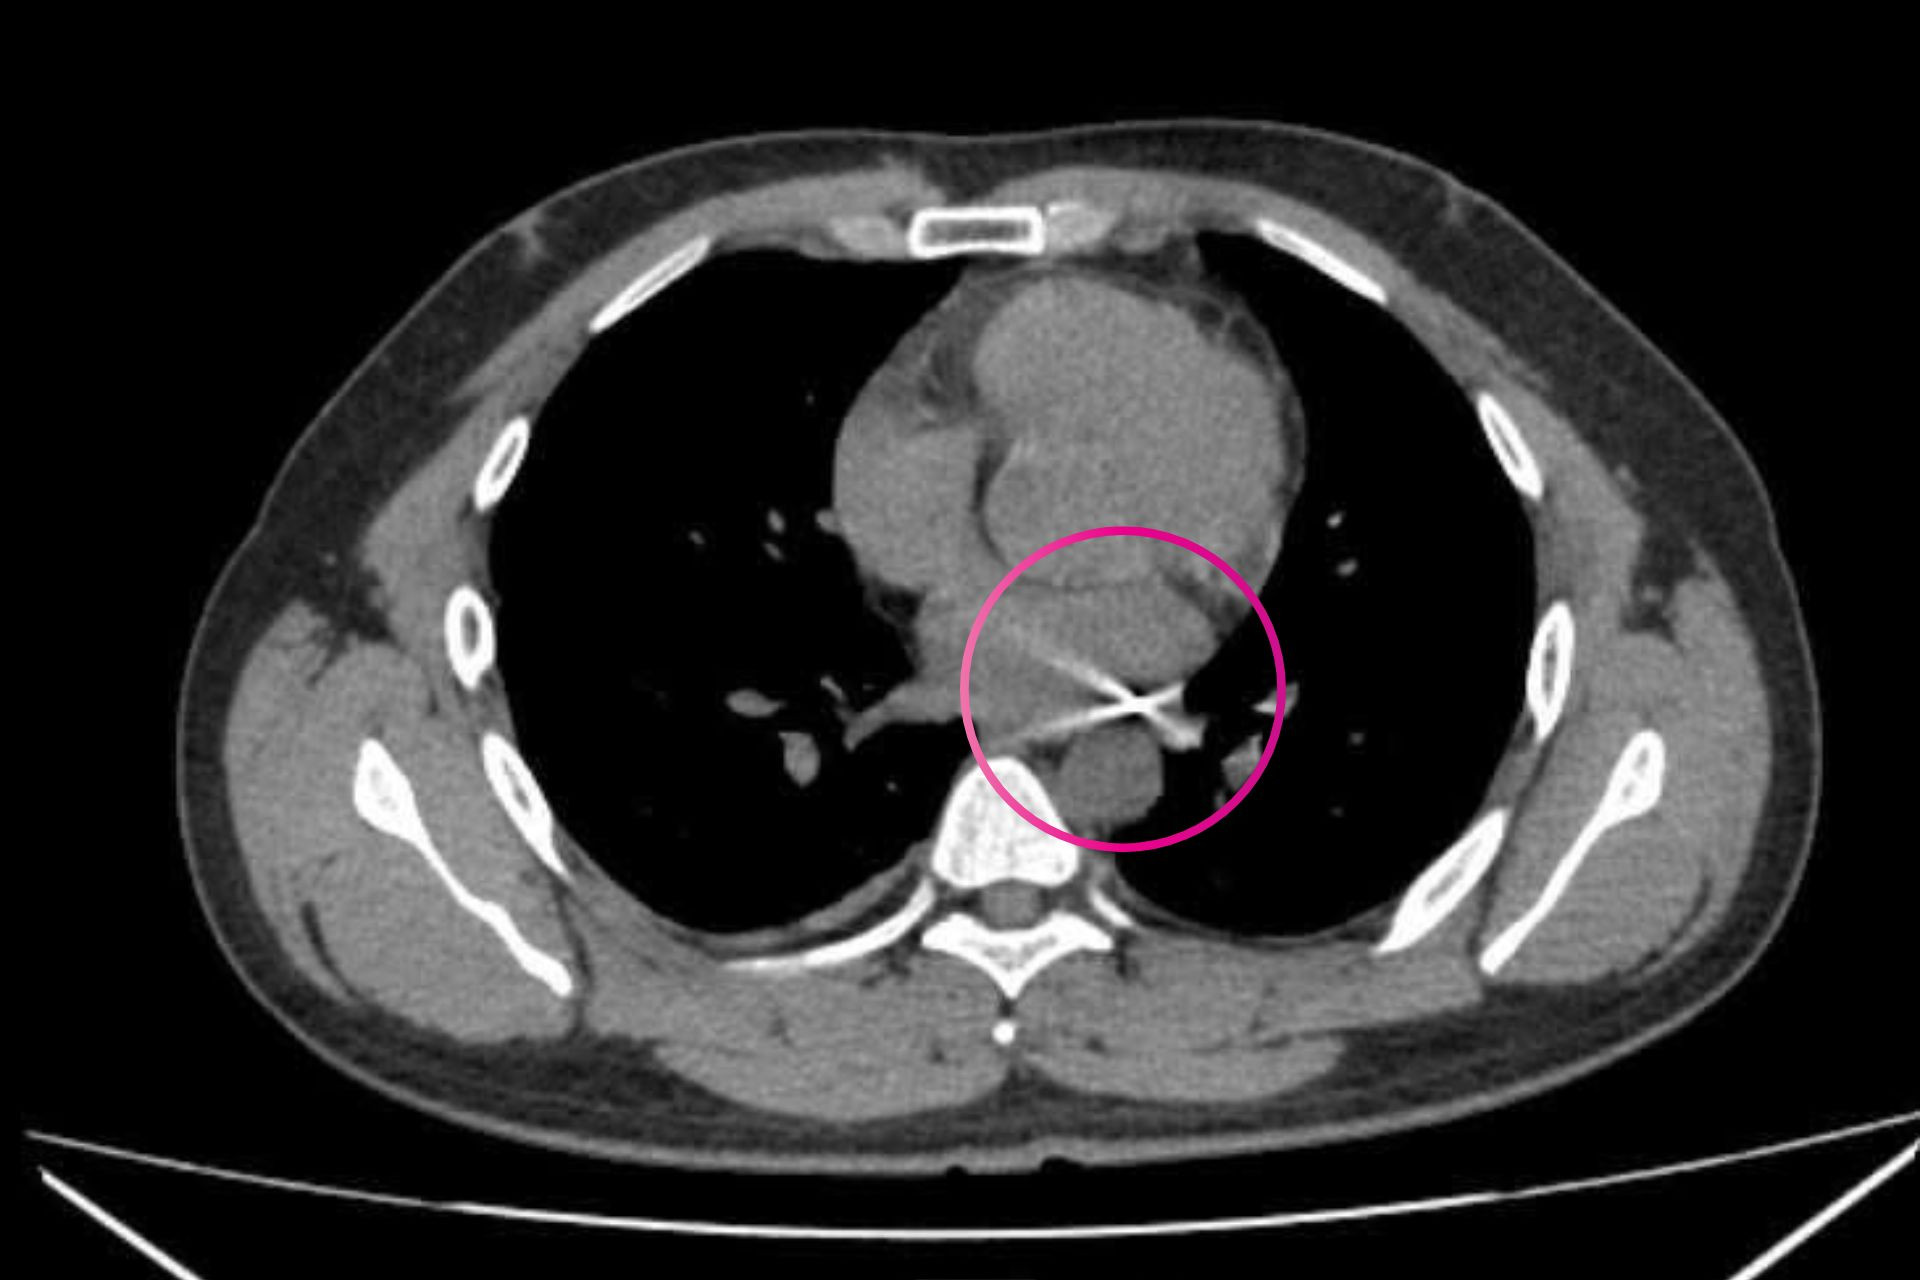

Quá trình kiểm tra, đầu đạn được phát hiện mắc kẹt tại vị trí góc giữa động mạch chủ và động mạch phổi. Sau hơn 4 giờ phẫu thuật, ê-kíp đã lấy ra đầu đạn kích thước khoảng 0,3 x 0,5cm.